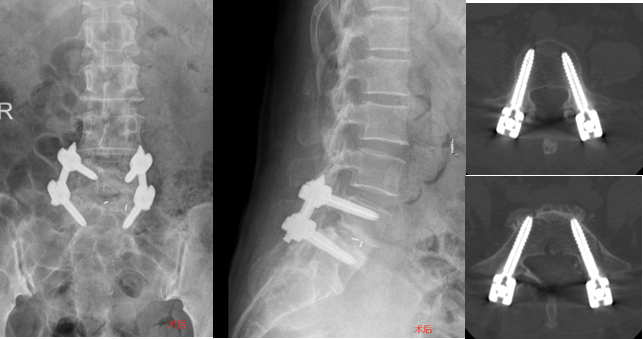

术前侧位X片显示,腰5、骶1椎体之间严重滑脱

术后影像显示,螺钉位置准确